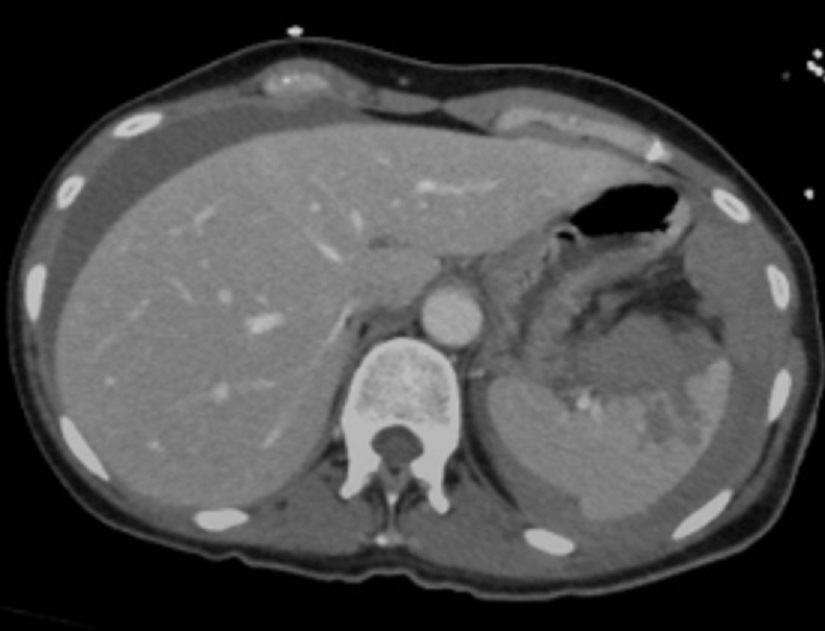

Image radiologique TDM

de hematome intra-parenchymateux de la rate est

aspect arrondie ou ovalaire hypodensite a contours

nette , moin regulier . Image radiologique d'une

traumatisme /contusion de la rate en coupe axiale |

Image radiologique TDM en

coupe axiale d'une traumatisme de la rate avec

aspect lesionnel de hematome intra-parenchymateuse

hypodense en forme ronde , lobulaire a bord nette et

irreguliers |